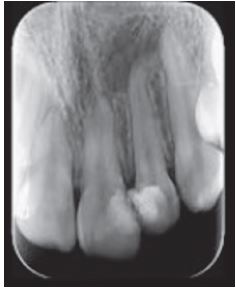

Se indicó una radiografía periapical del diente afectado, con la que se evidenció un área radiolúcida apical y para apical mesial de límites netos y forma redondeada (Figura 1).